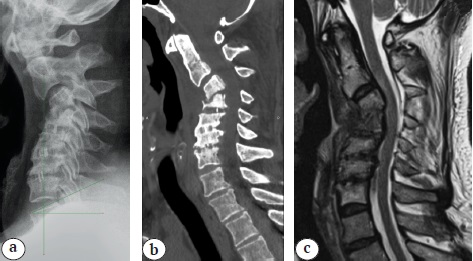

The patient was known to have a history of vertebrogenic cervical pain syndrome with irradiation to the left shoulder joint area since September 2020. He underwent staged courses of conservative analgetic (NSAIDs) and neurotropic therapy without any stable therapeutic effect. ENMG of the upper extremities (March 2021) showed the presence of preganglionic lesions of the C6-C8 spinal cord roots. MRI of the cervical spine in March 2021 revealed polysegmental degenerative-dystrophic changes in the C3-C7 spinal motion segments, stenosis of the spinal canal with the development of discoradicular conflict (Fig. 1).

Fig. 1. MRI (a — T2 images; b — STIR images): C3–С7 polysegmental degenerative changes, spinal canal stenosis, C6–С7 end plates oedema type I Modic, polysegmental myelopathy C4–С7

Considering the clinical picture and radiological findings, the patient underwent surgery in May 2021: anterior cervical discectomy, decompression of the spinal canal and interbody fusion at the C5-C6, C6-C7 levels (Fig. 2). Postoperative period was uneventful, and the radicular pain syndrome was partially resolved (intensity was up to 5 points according to VAS).

Fig. 2. MRI (a — T2 images; b — STIR images) and CT (c) after the first operation: two interbody implants (PEEK cages) are identified at the C5–С6, C6–С7, C4–С6 ossification of the posterior longitudinal ligament (segmental type according to the Committee on the Ossification of the Spinal Ligaments)